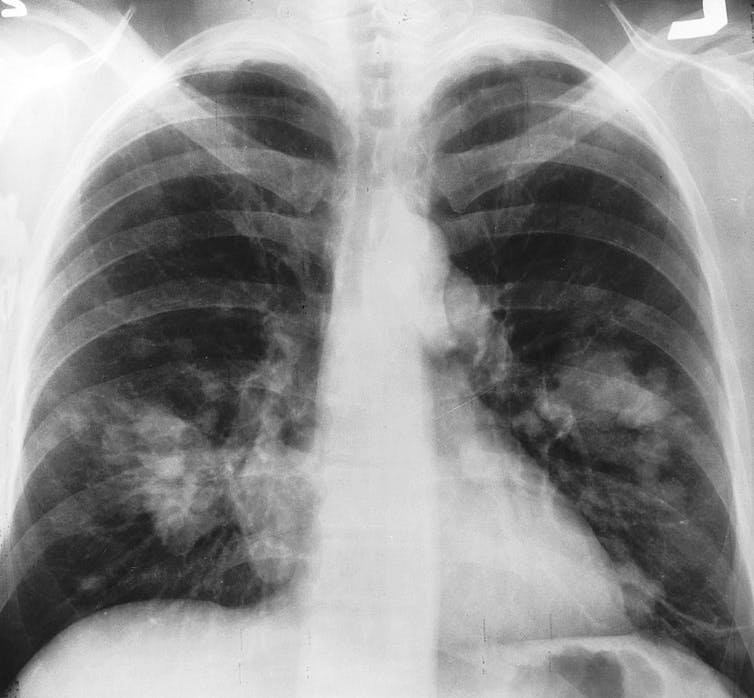

Aujourd’hui, et depuis les années 1960, le cancer du poumon est (de loin) la première cause de décès par cancer dans le monde. Le cancer du poumon (dont presque toutes les formes peuvent être attribuées au tabagisme) est responsable de 18 % de tous les décès par cancer en 2020 ; le cancer du foie étant la deuxième cause de décès la plus fréquente, avec 8,3 %.